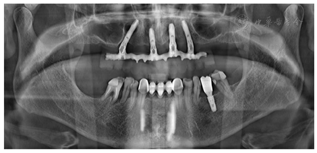

(1)种植一期手术:①阿替卡因肾上腺素注射液局麻下拔除上颌余留牙。②沿16-26区域牙槽嵴顶全层翻瓣,清除拔牙窝内炎性肉芽组织,平整牙槽嵴顶。③分别于12、22、25区定点,逐级备洞,12、22植入Nobel Speedy 4.0 mm×13 mm种植体;25近中倾斜植入Nobel Speedy 4.0 mm×15 mm种植体;④超声骨刀于13、14、15牙槽嵴顶8 mm处行唇、颊侧骨壁近远中向开窗,开窗面积约15 mm×8 mm,剥离上颌窦底黏膜后,15区定点,推开上颌窦底黏膜,近中倾斜备洞直达鼻底,倾斜植入Nobel speedy 4.0×18 mm种植体。⑤4颗种植体初期稳定性均达到35NCm,15颊侧骨开窗区种植体表面覆盖浓缩生长因子(Concentrated growth factor, CGF)(视频4)。⑥拔除18,12旋入RP17°3 mm复合基台,22旋入RP17°4 mm复合基台,15、25分别旋入RP 30°5 mm复合基台,修整牙龈组织,黏膜瓣复位、缝合创口,拍摄曲面体层片(图3)。

(2)即刻修复:制取上下颌硅橡胶印模,利用术前可摘局部义齿转移颌位关系,制作丙烯酸树脂临时固定义齿,咬合关系恢复至第二前磨牙,调整咬合。口内固定修复螺丝加力至15N.CM,牙龈硅橡胶封闭螺丝孔,拍摄曲面体层片(图4,图5)。

随访X线检查示4颗种植体周围骨结合良好(图10,图11J,图12J,图13,图15)。